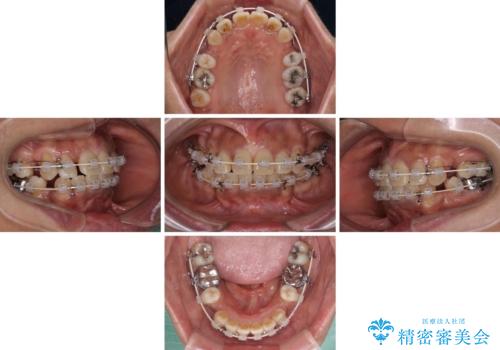

- 審美装置

- 2年4ヶ月

- 10-30回

- 八重歯やクロスバイトを気にして来院された患者様です。

口元の突出感はありませんでしたが、デコボコが強く、非抜歯矯正とすると出っ歯仕上がりとなる可能性があったため、上下左右の第一小臼歯4本を抜歯し、ワイヤー装置にて矯正治療を行うこととしました。